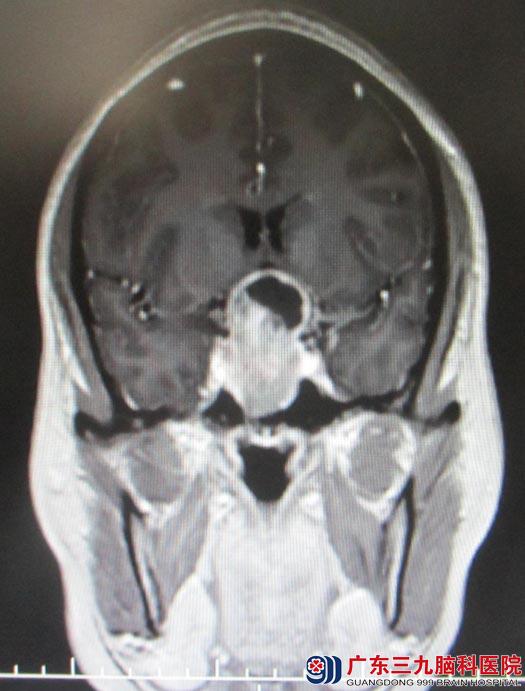

艾女士在半年前开始出现月经失调,经期延长,经量稀少,常规妇科检查未见明显异常,予中药调理,效果欠佳;并逐渐出现双眼视物模糊,当地医院头颅CT检查提示“鞍区占位”。广东三九脑科医院头颅MRI检查结果:“鞍区占位,大小约3cm×4cm,考虑垂体瘤”。诊断:鞍区占位,垂体大腺瘤。

综合神经外科鲁明主任阅片后认为:患者月经紊乱,双眼视力及视野障碍,结合头颅MR检查,肿瘤体积大,鞍内、鞍上均有生长,手术指征明确,经鼻蝶手术,手术创伤小,手术时间短,术后恢复快,但一次手术不一定能全切肿瘤,如果肿瘤术后有残留,术后可能需要行再次手术或者放射治疗。

手术前

手术后